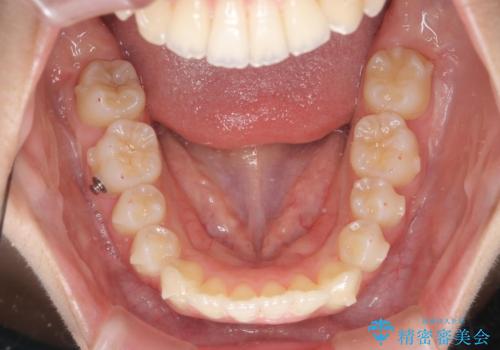

- 5年前にワイヤー矯正治療を終了したが、突き出たように見える前歯の仕上がりが気に入らず、再矯正治療を希望され来院されました。

マイクロインプラントを用いた遠心移動とIPRを行うことによる前歯の突出感の改善をマウスピース矯正治療で計画します。

突出していた前歯の角度が大きく改善し、審美的な仕上がりに満足いただくことができました。